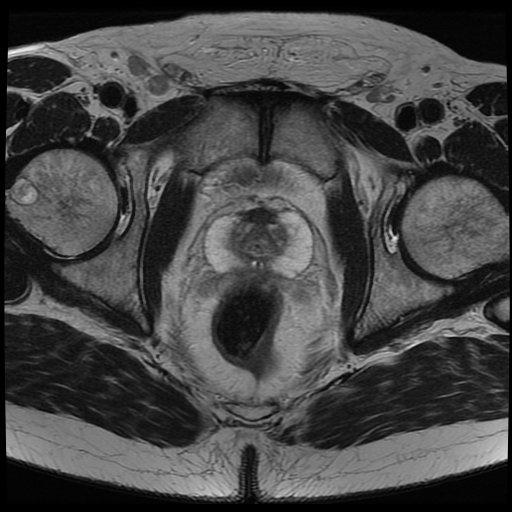

白色文字(排除指定关键词) Imaging Anatomy: interactive PACS-like atlas of radiological anatomy

解剖学模块